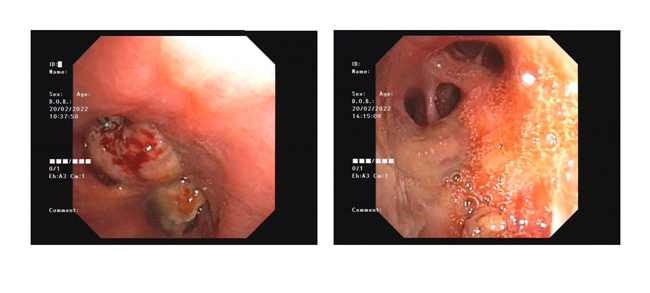

支气管镜下微波消融术前后对比

据黄德良主任介绍,刘健患者这次因肺鳞癌引起气喘问题过来求治的。入院后经过完善检查诊断为右肺鳞癌并胸膜、肺门、纵膈淋巴结转移,已是T4N2M1属于肺癌IV期了。“当时情况非常紧迫,患者右主支气管主干完全堵塞,左主支气管堵塞,虽然之前在外院做了支架,但支架近端也有肿瘤导致大部分的堵塞。病人呼吸困难,经皮血氧低于80%。在麻醉科,气管镜室和8楼医护共同努力下给病人行右主支气管肿物微波消融术,术后气道恢复通畅,右肺完全复张!患者手术中还出行反复出血,情况非常不理想,幸得患者家属无条件的信任,经过团队的共同努力,历时3个多小时的手术还是顺利完成。目前病人已经可以下床走路,经皮血氧恢复至95%。”2月15日,经过黄教授团队的评估后,患者接受了介入化疗方案,术后患者呼吸困难症状得到进一步改善,指尖血氧好转。在2月20日再次接受气管镜下双侧主支气管肿物微波消融术。3月1日复查了CT,患者肿块缩小,右肺复张。